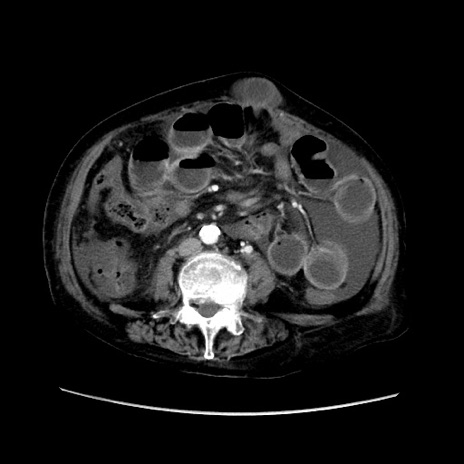

症例31(横断像)

【症例】80歳代 女性

【主訴】腹部膨満感

【現病歴】他院にて肝硬変にてフォロー中。1週間前から便秘、腹部膨満感、臍部腫瘤あり受診となる。

【既往歴】肝硬変

【身体所見】腹部膨隆あり、皮膚変化なし、疼痛なし。

【データ】WBC 4600、CRP 0.25